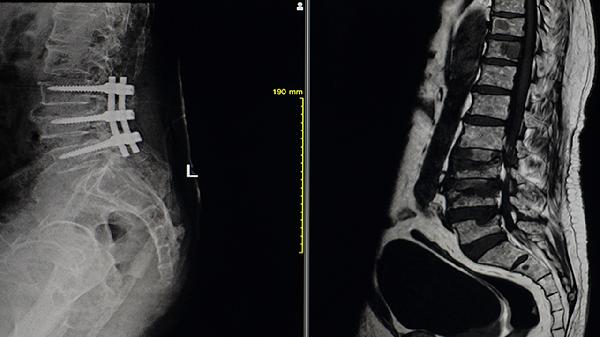

對Cobb角超過50度的進展性側(cè)彎,需行后路椎弓根螺釘固定融合術(shù)。術(shù)前需評估椎弓根發(fā)育情況,術(shù)中采用骨水泥強化螺釘把持力。嚴重骨質(zhì)疏松者需分期手術(shù)。